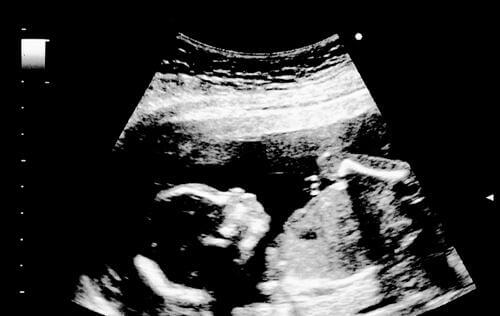

Pendant la dix-huitième semaine de grossesse, le bébé mesure 14 centimètres ou 5 pouces et demi. Il pèse environ 190 grammes. Ses mouvements sont chaque fois plus vigoureux. Sur l’échographie, on pourra le voir étirer et contracter ses extrémités. On pourra également le voir ouvrir et fermer la bouche alors qu’il apprend à avaler.

L’on peut apercevoir ses vaisseaux sanguins grâce à la transparence de la peau. Les sourcils et les cils commencent à apparaître. Ses oreilles et ses yeux sont à leur place. Lors de l’échographie, l’on peut observer le bébé qui met ses doigts à la bouche.

On peut également le voir bailler ou faire des grimaces. Certains bébés ont même le hoquet pendant la grossesse. On pourra même le voir sauter dans son espace naturel.